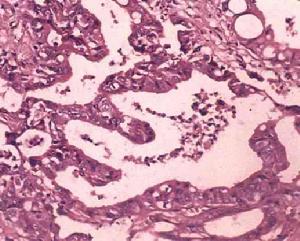

2、組織學分類:95%以上的膽管癌為腺癌,少數為鱗狀上皮癌、黏液癌,囊腺癌等,在原發性肝外膽管癌中,以膽總管癌最多見,33%~40%;其次為肝總管癌,30%~32%;肝總管分叉處,為20%;膽囊管4%。肝外膽管癌組織學缺乏統一的分類,常用的是按癌細胞類型分化程度和生長方式分為6型:①乳頭狀腺癌;②高分化腺癌;③低分化腺癌;④未分化癌;⑤印戒細胞癌;⑥鱗狀細胞癌等,以腺癌多見。分型研究報告各家不盡一致,但最常見的組織學類型仍為乳頭狀腺癌、高分化腺癌,占90%以上,少數為低分化腺癌與黏液腺癌,也有罕見的膽總管平滑肌肉瘤的報告等。

3、肝外膽管癌的組織學類型:根據癌細胞的類型,分化程度及癌組織生長方式。肝外膽管癌可分為以下6型:⑦乳頭狀腺癌:除個別為管壁浸潤型外,幾乎均為腔內乳頭狀型。②高分化腺癌:在膽管癌中最多,可占2/3以上,可見於任何部位。癌組織均在管壁內浸潤生長,環繞整個管壁。浸潤的癌組織呈大小不等,形狀不規則的腺體結構,有的可擴大呈囊腔。③低分化腺癌:即分化差的腺癌,癌組織部分呈腺體結構,部分為不規則的實性片塊,亦在管壁內瀰漫浸潤生長。④未分化癌:較少見。有的小細胞未分化癌,與膽囊的未分化癌相同,癌細胞在膽管壁內瀰漫浸潤,間質較少。癌組織侵襲較大,常可侵及膽管周圍脂肪組織或鄰近的器官。⑤印戒細胞癌:較少見。它與膽囊或胃腸道的印戒細胞癌一樣,由分化程度不等的含有粘液的癌細胞構成。癌細胞無一定結構,瀰漫浸潤。⑥鱗狀細胞癌:罕見。其組織形態與其他器官所見者相同。